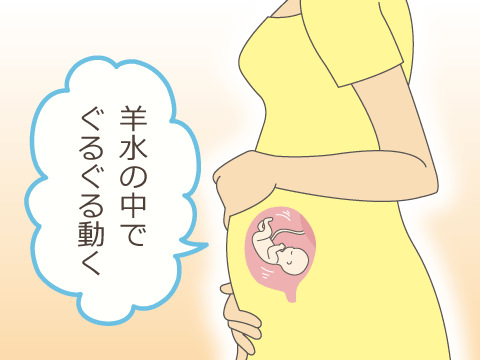

mediskin_official 👈他の投稿はこちら👶🏻妊娠中期のお腹の張り安定期に入る妊娠中期のお腹の張りは、体を動かすことへの反応 生理的な張り の場合がほとんどです💡張りを感じた場合は、ベットに横になったりソファに座ったりと、体を休ませてあげましょう。

妊娠中期のお腹の張りはなぜ起こる?原因と改善方法をご紹介HAPPINESS! magazine ハピネスマガジン。

妊娠中期からのおなかの張り、「危険な張り」と「安全な張り」の違いは?たまひよ。